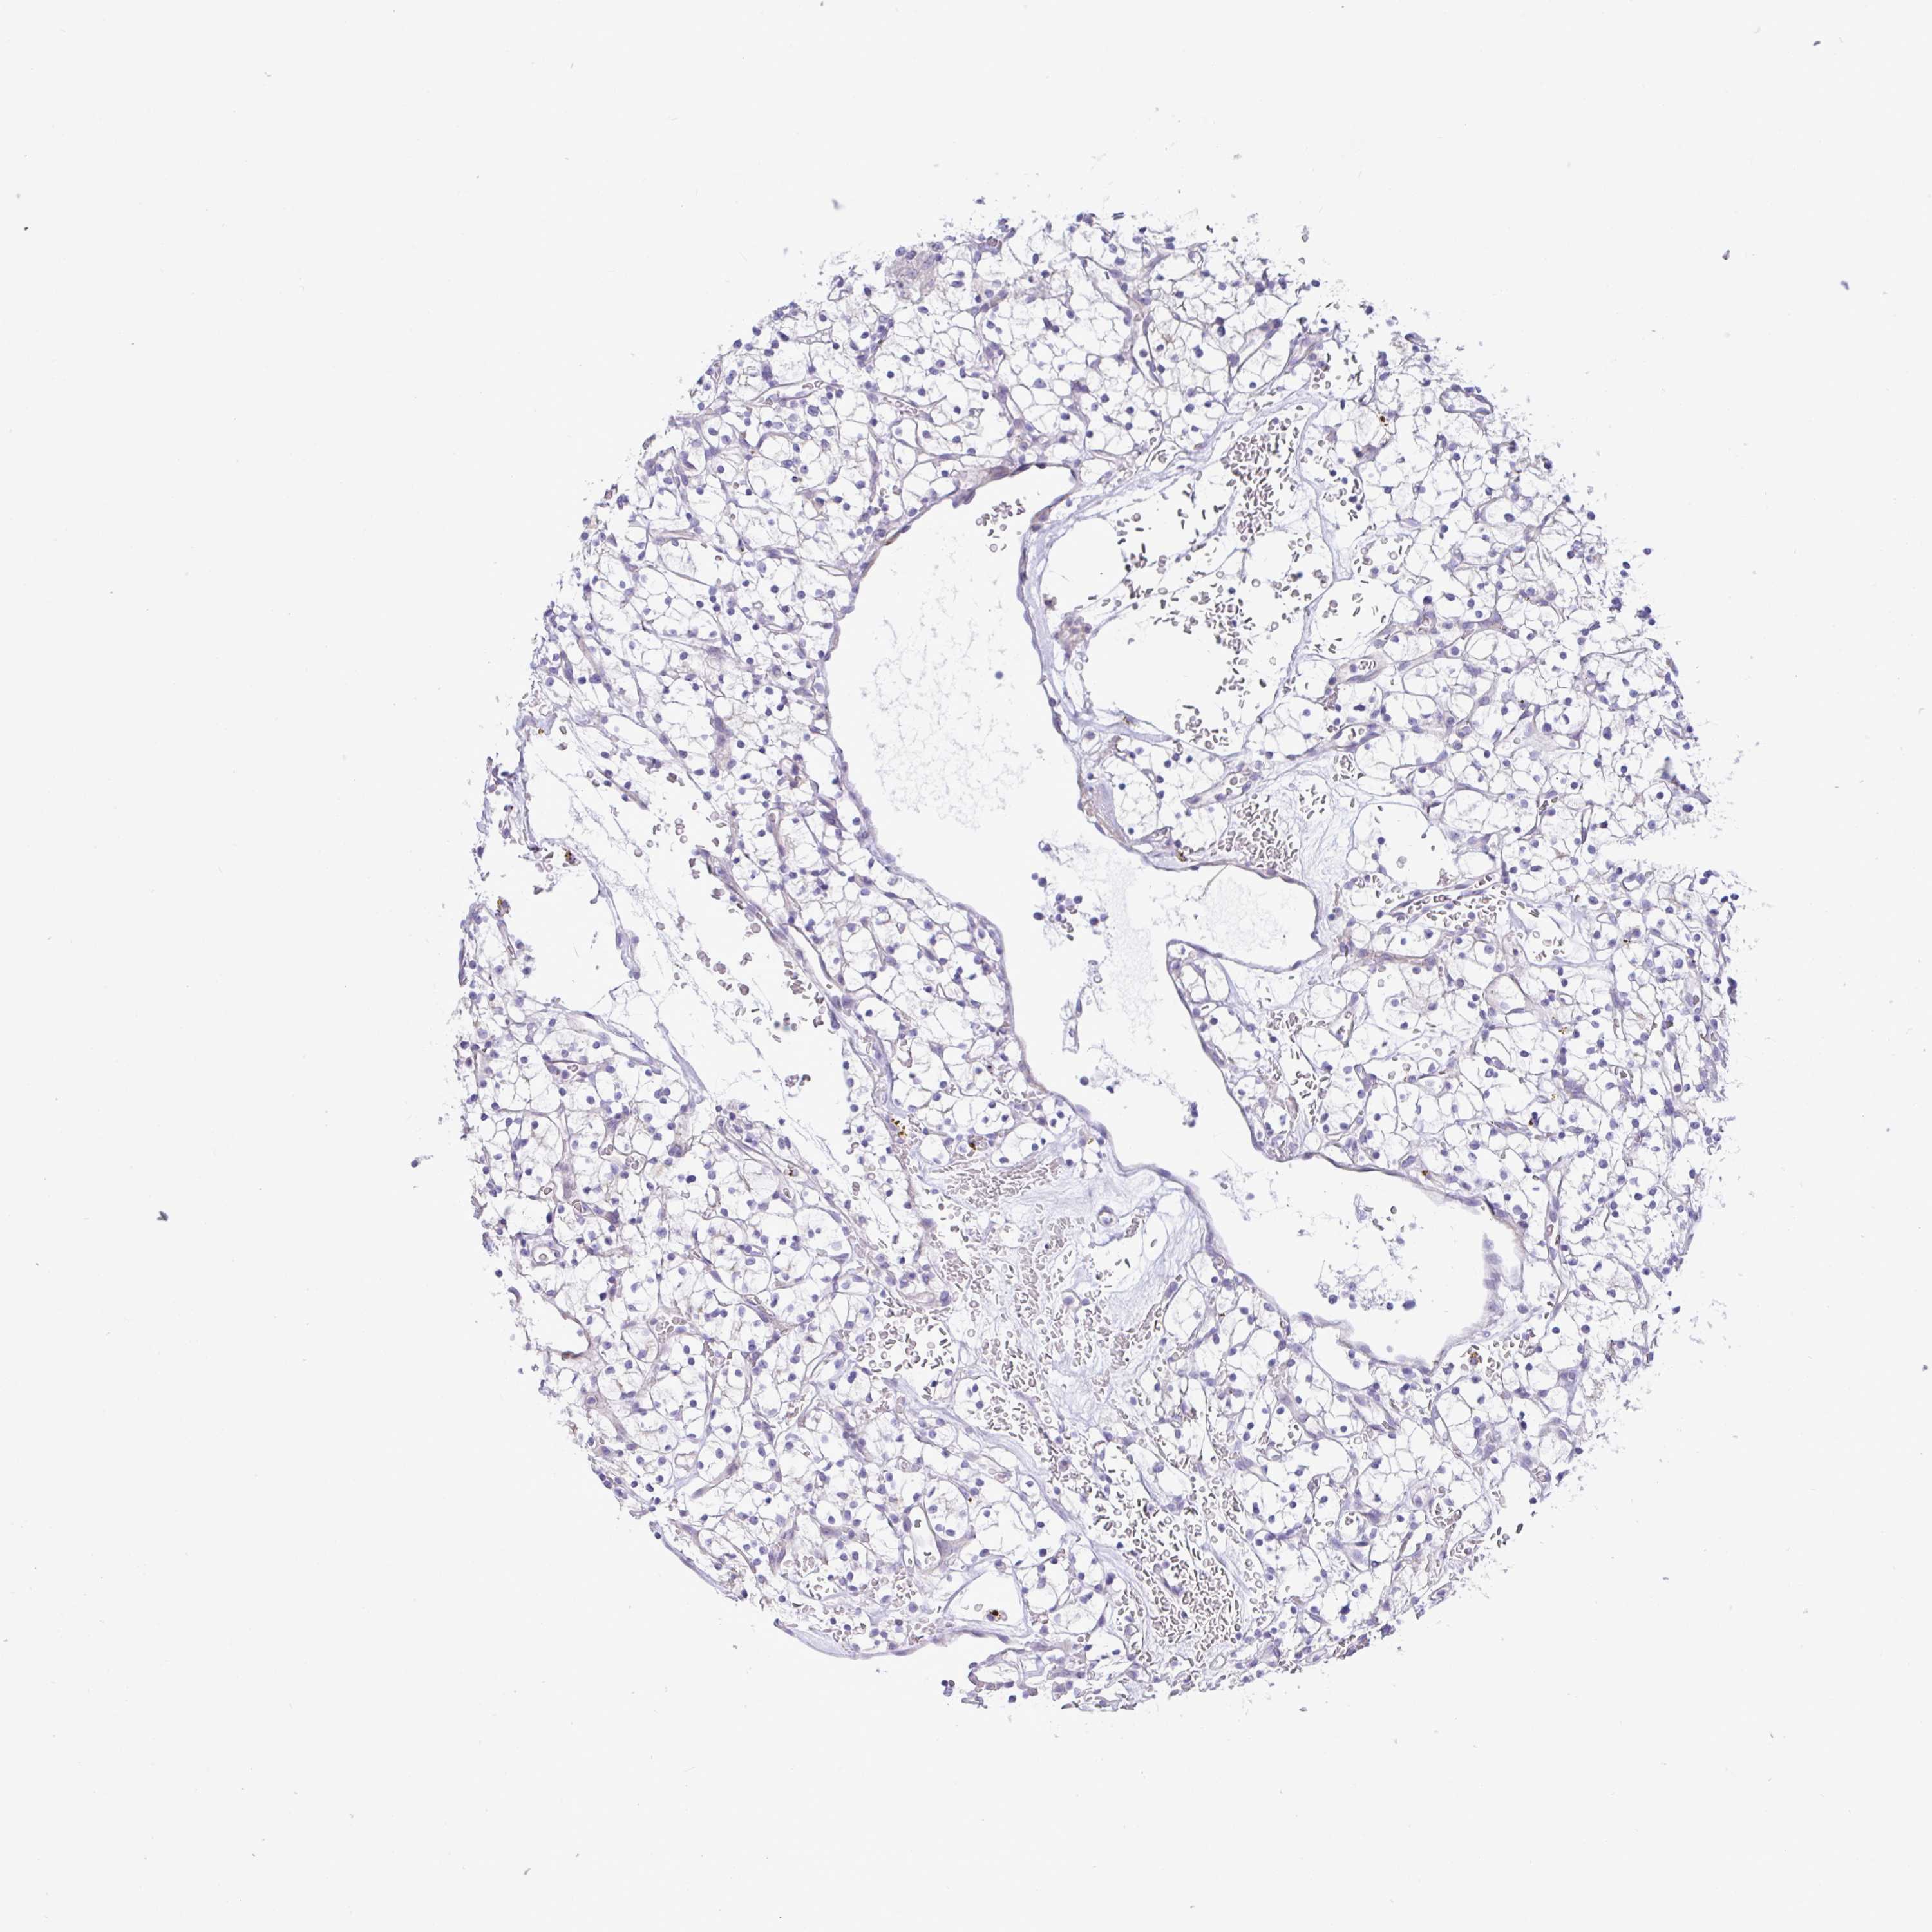

KIDNEY CHROMOPHOBE (TCGA) - Interactive survival scatter ploti

The Survival Scatter plot shows the clinical status (i.e. dead or alive) for all individuals in the patient cohort, based on the same data that underlies the corresponding Kaplan-Meier plots. Patients that are alive at last time for follow-up are shown in blue and patients who have died during the study are shown in red.

The x-axis shows the expression levels (FPKM) of the investigated gene in the tumor tissue at the time of diagnosis. The y-axis shows the follow-up time after diagnosis (years). Both axes are complimented with kernel density curves demonstrating the data density over the axes. The top density plot shows the expression levels (FPKM) distribution among dead (red) and alive patients (blue). The right density plot shows the data density of the survived years of dead patients with high and low expression levels respectively, stratified using the cutoff indicated by the vertical dashed line through the Survival Scatter plot. This cutoff is automatically defined based on the FPKM cutoff that minimizes the p-score. The cutoff can be changed by dragging the vertical line or by entering a cutoff value in the square labeled "Current cut-off".

Under the Survival Scatter plot the p-score landscape (black curve; left axis) is shown together with dead median separation (red curve; right axis). Dead median separation is the difference in median mRNA expression between patients who have died with high and low expression, respectively. It is calculated as follows: median FPKM expression of dead patients with high expression - median FPKM expression of dead patients with low expression. This is intended to aid the user in visually exploring custom cutoffs and the associated p-scores and dead median separation.

Individual patient data is displayed and can be filtered by clicking on one or more of the category buttons on the top of the page. Categories describing expression level and patient information include: high, low, alive, dead, female, male and tumor stages. The scale of the x-axis can be toggled between linear and log-scale by clicking on the "x log" button. Mouse-over function shows TCGA ID, patient information and mRNA expression (FPKM) for each patient.

& Survival analysisi

Kaplan-Meier plots summarize results from analysis of correlation between mRNA expression level and patient survival. Patients were divided based on level of expression into one of the two groups "low" (under cut off) or "high" (over cut off). X-axis shows time for survival (years) and y-axis shows the probability of survival, where 1.0 corresponds to 100 percent.

MED11 is not prognostic in Kidney Chromophobe (TCGA)